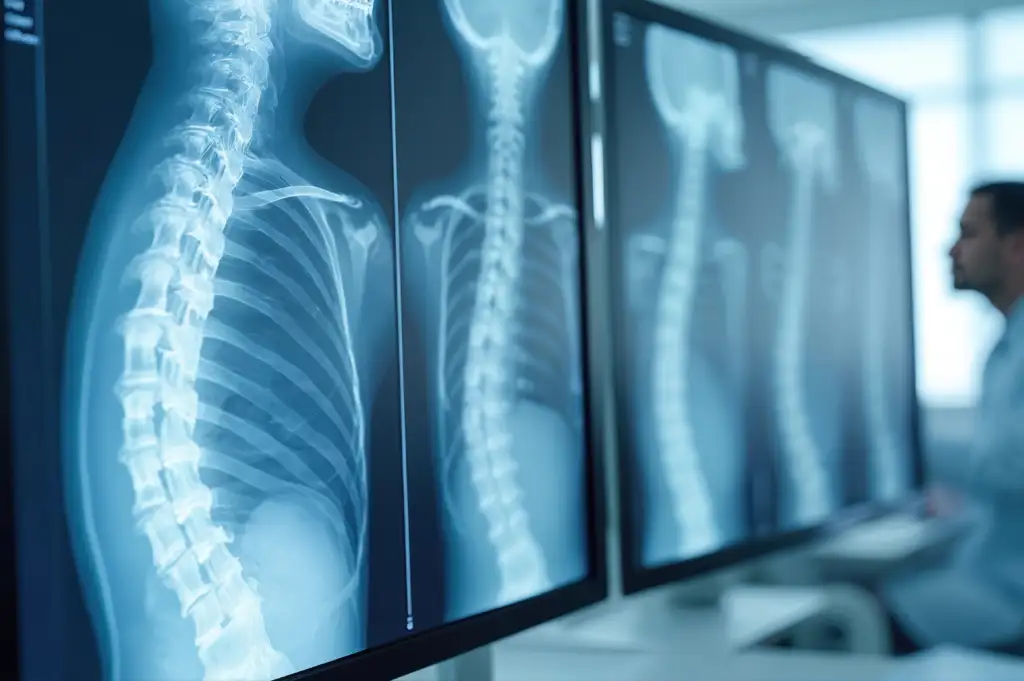

Die Wirbelsäulenmedizin befasst sich mit einem breiten Spektrum an Erkrankungen und Verletzungen, die von degenerativen Veränderungen bis hin zu akuten Traumata reichen. Dazu gehören degenerative Erkrankungen wie Bandscheibenvorfälle oder Spinalkanalstenosen, entzündliche und infektiöse Krankheiten der Wirbelsäule, Deformitäten wie Skoliosen oder Fehlhaltungen sowie stoffwechselbedingte Erkrankungen wie Osteoporose.

Auch Frakturen der Hals-, Brust- und Lendenwirbelsäule sowie Beschwerden im Bereich des Iliosakralgelenks (ISG-Syndrom) zählen zu den typischen Krankheitsbildern, die in der Wirbelsäulenmedizin diagnostiziert und behandelt werden.